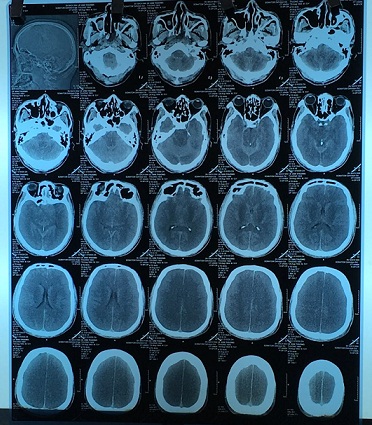

Kết quả chụp phim cho thấy: não bị phù, căng cả 2 bên. Dấu hiệu gợi ý nhu mô não tổn thương nặng và lan rộng cả 2 bên. Nồng độ methanol trong máu là 210 mg/dL (gấp nhiều lần so với nồng độ gây tử vong, khoảng 40 – 50 mg/dL đã là rất nặng). Bệnh nhân đã được cấp cứu, hồi sức, lọc máu thải độc, dùng các thuốc giải độc nhưng do đến muộn và não tổn thương quá nặng, tử vong cận kề nên gia đình xin về để mất tại nhà.

| Hình ảnh phim chụp não của bệnh nhân bị ngộ độc methanol nặng |